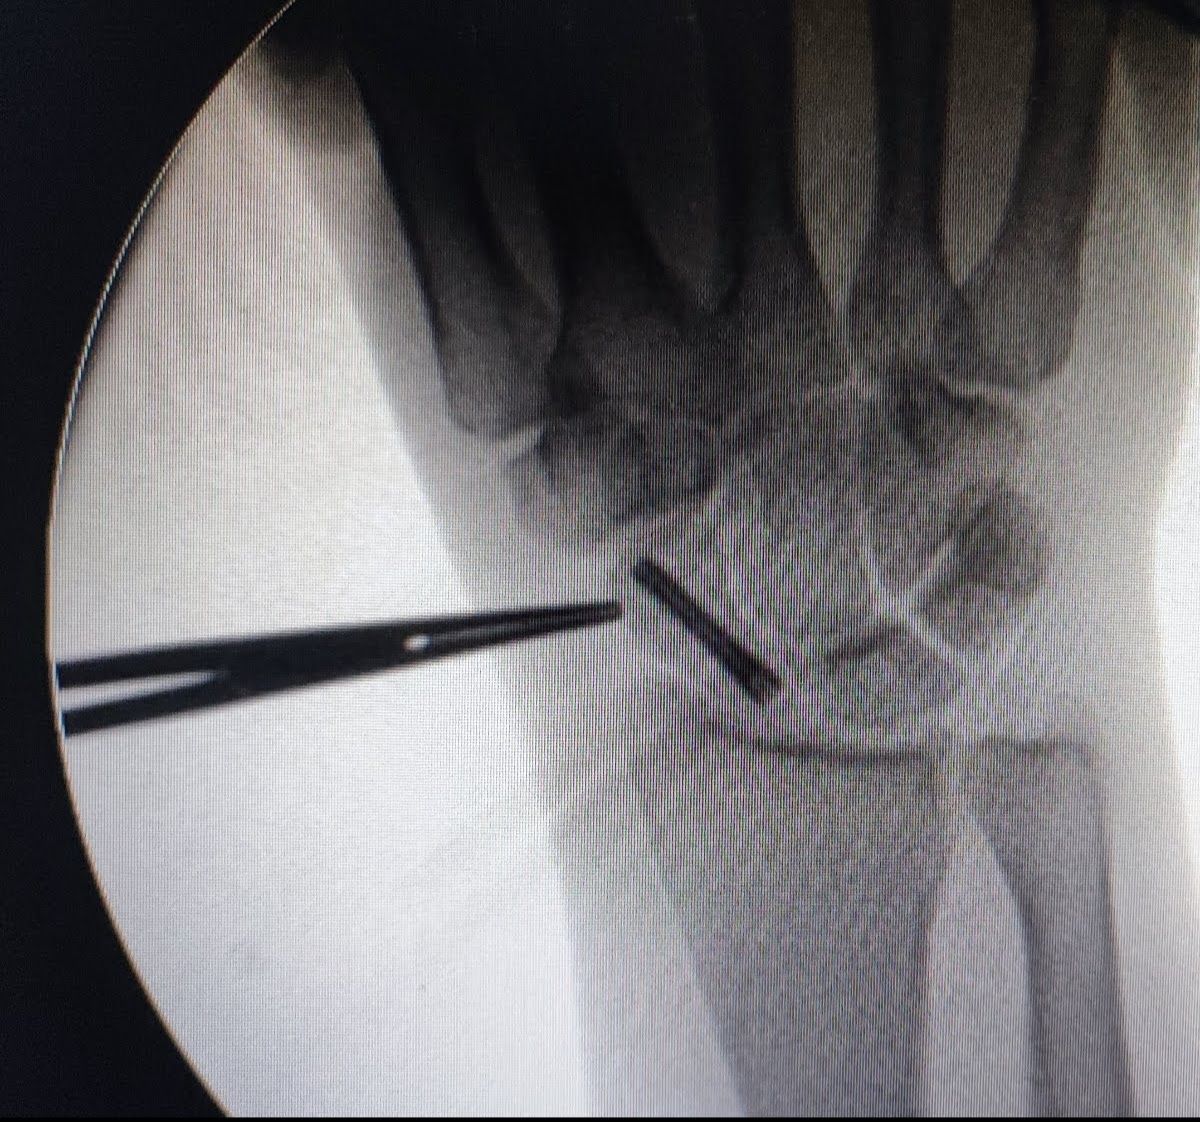

Il Dott. Emanuele Gerace si è laureato in Medicina e Chirurgia presso l'Universita di Roma "La Sapienza" con voto di 110/110 e lode, poi si è specializzato con lode in "Ortopedia e Traumatologia" presso l'Università di Ferrara. Ha completato il suo percorso formativo in Francia presso l'Institut de la Main di Nantes, il Kaplan Hand Institut di Barcellona in Spagna ed in Italia nel centro di chirurgia della mano dell'Hesperia Hospital di Modena e nel centro di chirurgia artroscopica e mini invasiva del ginocchio e della spalla. Nel 2022 ha conseguito il Diploma avanzato di Microchirurgia presso la Società Italiana di Microchirurgia. Si è formato in Artroscopia di polso presso l'IRCAD di Strasburgo, Francia. Ha lavorato per 5 anni come Dirigente Medico presso l'Ospedale Maggiore di Cremona. L'ambito di interesse primario è la chirurgia della mano e del polso. Attualmente svolge la propria attività clinica e chirurgica presso la Fondazione Policlinico Gemelli IRCCS.

Esperto in Chirurgia della Mano.